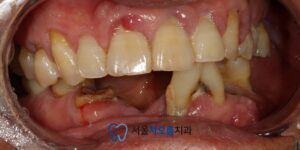

환자분께서는

아래쪽 치아의 상실된 부분이 많고

남아있는 치아도 온전치 않아

식사하기 불편하시다며

내원해주셨습니다.

확인해보니,

아래쪽 치아들의 상실된 부분도 있고,

남아있는 치아들의 예후도

안좋았는데요.

오른쪽 아래 큰 어금니는

뿌리 하방으로 염증이

크게 잡혀있었습니다.

관리가 잘 되지 않아

치석이 많이 쌓여 있었고,

여러 부위에서 충치도

깊게 진행된 상태였습니다.

25.03.21 / 25.07.06

치료 전후 사진입니다.